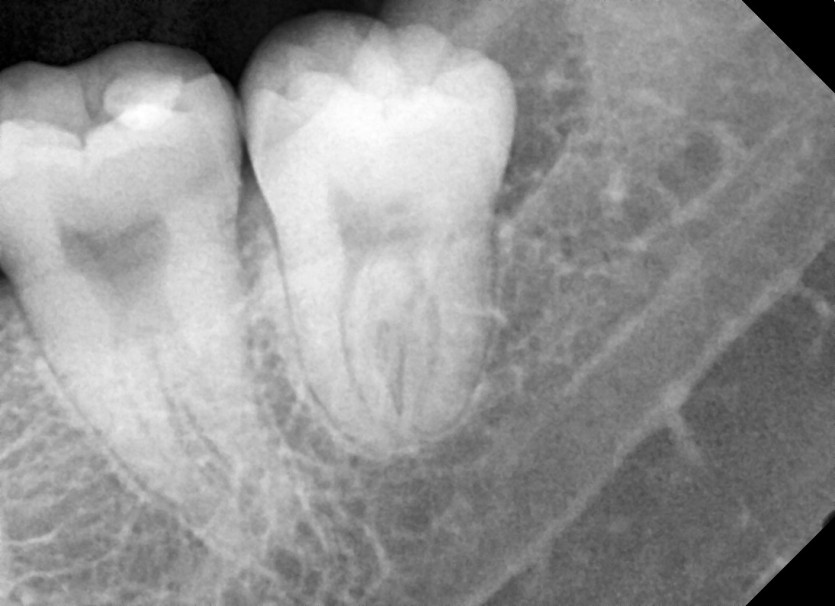

#28,38 사랑니 발치

구강 외과 전문의가 당일 발치했습니다.